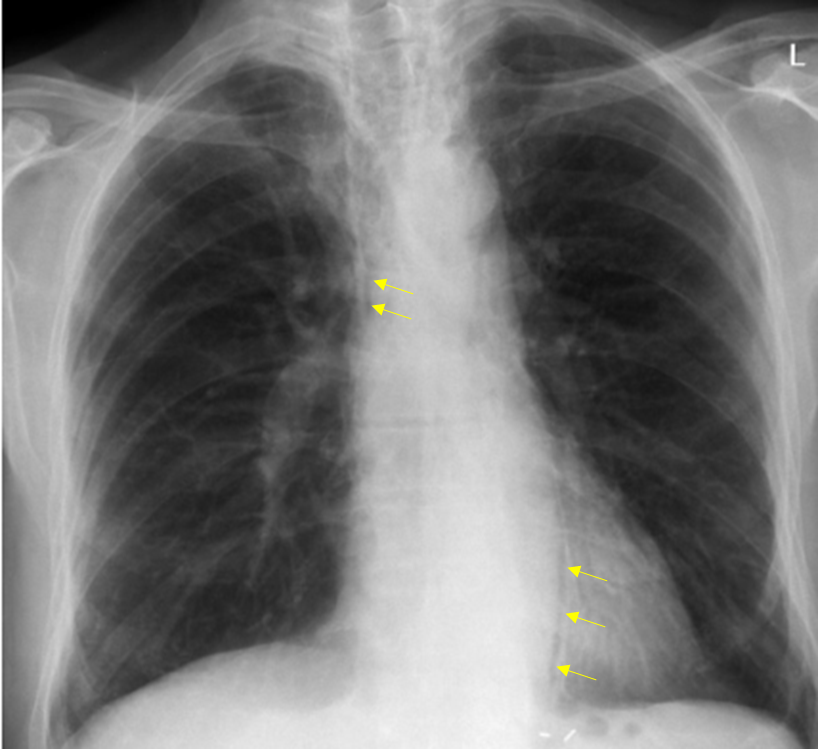

65세 남자가 3시간 전부터 찌르는 듯한 윗가슴 통증으로 병원에 왔다. 1개월 전에 비소세포폐암 3B병기로 진단받고 항암방사선 동시요법을 받았다. 구역, 식욕저하, 윗가슴 통증으로 식도염이 의심되어 간헐적으로 방사선치료가 중단되곤 했다고 한다. 혈압 115/70 mmHg, 맥박 110회/분, 호흡 24회/분, 체온 37.7 ℃이다. 목과 앞가슴이 부어 있었고, 가슴 청진에서 양쪽 윗가슴의 호흡음이 감소하였다. 혈액검사 결과는 다음과 같다. 가슴 X선사진이다. 검사는?

Img | CXR: Pneumomediastinum |

Imp: 종격동기종(pneumomediastinum)

R/O 급성 종격동염(acute mediastinitis)

Acute sharp chest pain과 CXR상 확인되는 pneumomediastinum으로 보아 원인 감별 등을 위해 chest CT가 필요하다.

• CXR상 아래와 같이 mediastinum 쪽의 pleural line이 확인되어 pneumomediastinum으로 진단할 수 있다.

• WBC 상승, BT 37.7이 동반되므로 acute mediastinitis도 의심해볼 수 있다.

• 따라서 Chest CT를 통해 pneumomediastinum의 위치 및 원인을 확인하는 것이 중요하다.